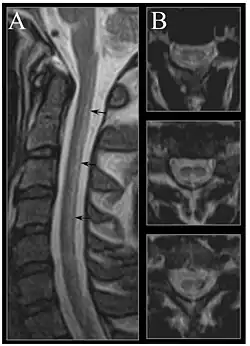

| Image of the cervical spinal cord in vitamin B12 deficiency showing subacute combined degeneration. (A) The midsagittal T2-weighted image shows linear hyperintensity in the posterior portion of the cervical tract of the spinal cord (black arrows). (B) Axial T2-weighted images reveal the selective involvement of the posterior columns. | |

MRI of the brain may show periventricular white matter abnormalities. MRI of the spinal cord may show linear hyperintensity in the posterior portion of the cervical tract of the spinal cord, with selective involvement of the posterior columns.